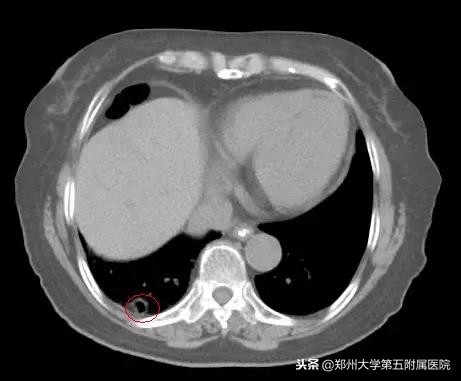

陶女士听到这样的解释非常满意立即让母亲接受了1疗程的治疗,患者的声嘶呛咳症状渐渐好转。为了寻找原发病灶的蛛丝马迹,丁主任让患者再次复查胸部增强CT,通过一帧帧仔细的分析影像资料,找到了一个小小的空洞病灶,通过与之前的影像资料对比,丁主任指出高度怀疑这个病灶有问题!马上请放射影像科吴峰医生为患者做CT引导下经肺穿刺检查(PTLB),病理结果是:中分化鳞状细胞癌。

原发病灶终于找到了!就是这个小小的空洞,曾经因为太小而被误诊为炎症空洞,每一个小小的忽视就有可能耽误患者的确诊和治疗,只有医生拥有较强的专业性和更多的耐心才能不放过任何隐匿的“敌人”。对于这个原发病灶,丁主任建议李奶奶再次进行伽玛刀治疗,以控制原发灶的发展,伽马射线犹如外科手术般精确对肿瘤细胞进行进行摧毁。

▲ 上图为曾被误诊为炎症的薄壁空洞,下图为增厚的空洞病灶,经穿刺后确诊为肺鳞癌的原发病灶